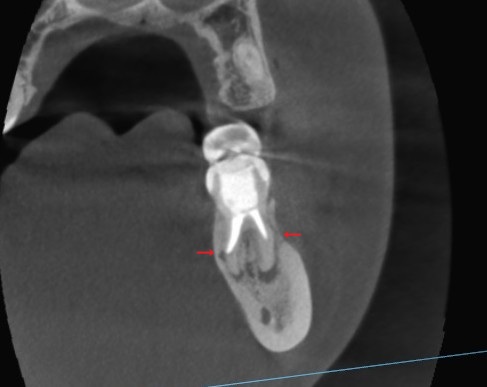

遠心の歯根の断面です。

左側の根管ですが、本来の根管へ修正し、充填しているのが分かります。

右側も根の先まできれいに繋げています。